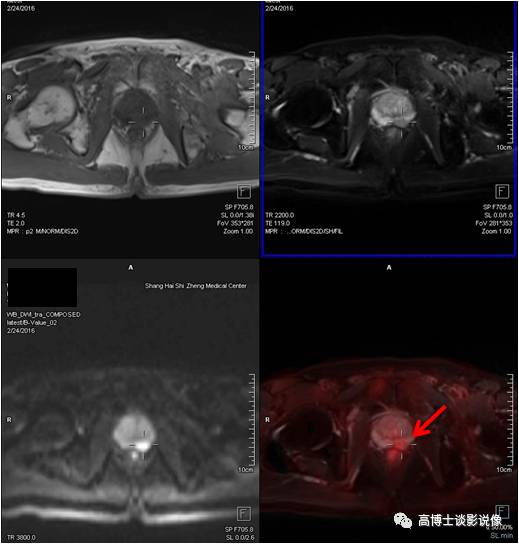

PET/MR

骨骼系统

血管瘤

老年男性,无明显不适,体检发现铁蛋白升高。胸12、腰3椎体各见一类圆形异常信号灶,边界清楚,长径分别为1.3cm、1.8cm,诊断为血管瘤。

点评

脊柱血管瘤是一种常见的良性肿瘤,一般无症状,通常在颈腰椎CT或MRI检查中偶然发现。MRI显示血管瘤的形态、边界优于CT,PET/MRI可以帮助鉴别是否为侵袭性血管瘤,或与脊柱其他肿瘤鉴别。

骨样骨瘤

青年女性,右侧髂骨见一大小约1.3*0.8cm椭圆形异常信号灶,边界清楚,FDG代谢增高,考虑为骨样骨瘤。

骨样骨瘤为良性成骨性肿瘤。常见于常见于30岁以下的青少年。临床表现局限的疼痛,对口服水杨酸盐药物可以使疼痛缓解。对症状较轻者,可行保守治疗,定期复查。有部分患者可以自愈,症状逐渐消失。

内生软骨瘤

青年男性,右侧肱骨近端骨髓腔内类圆形异常信号灶,长径约2.6cm,FDG轻度摄取增高,考虑为内生软骨瘤。

单发性内生性软骨瘤生长缓慢,病灶小,可长期无症状,注意避免剧烈外伤史,定期随访观察即可。